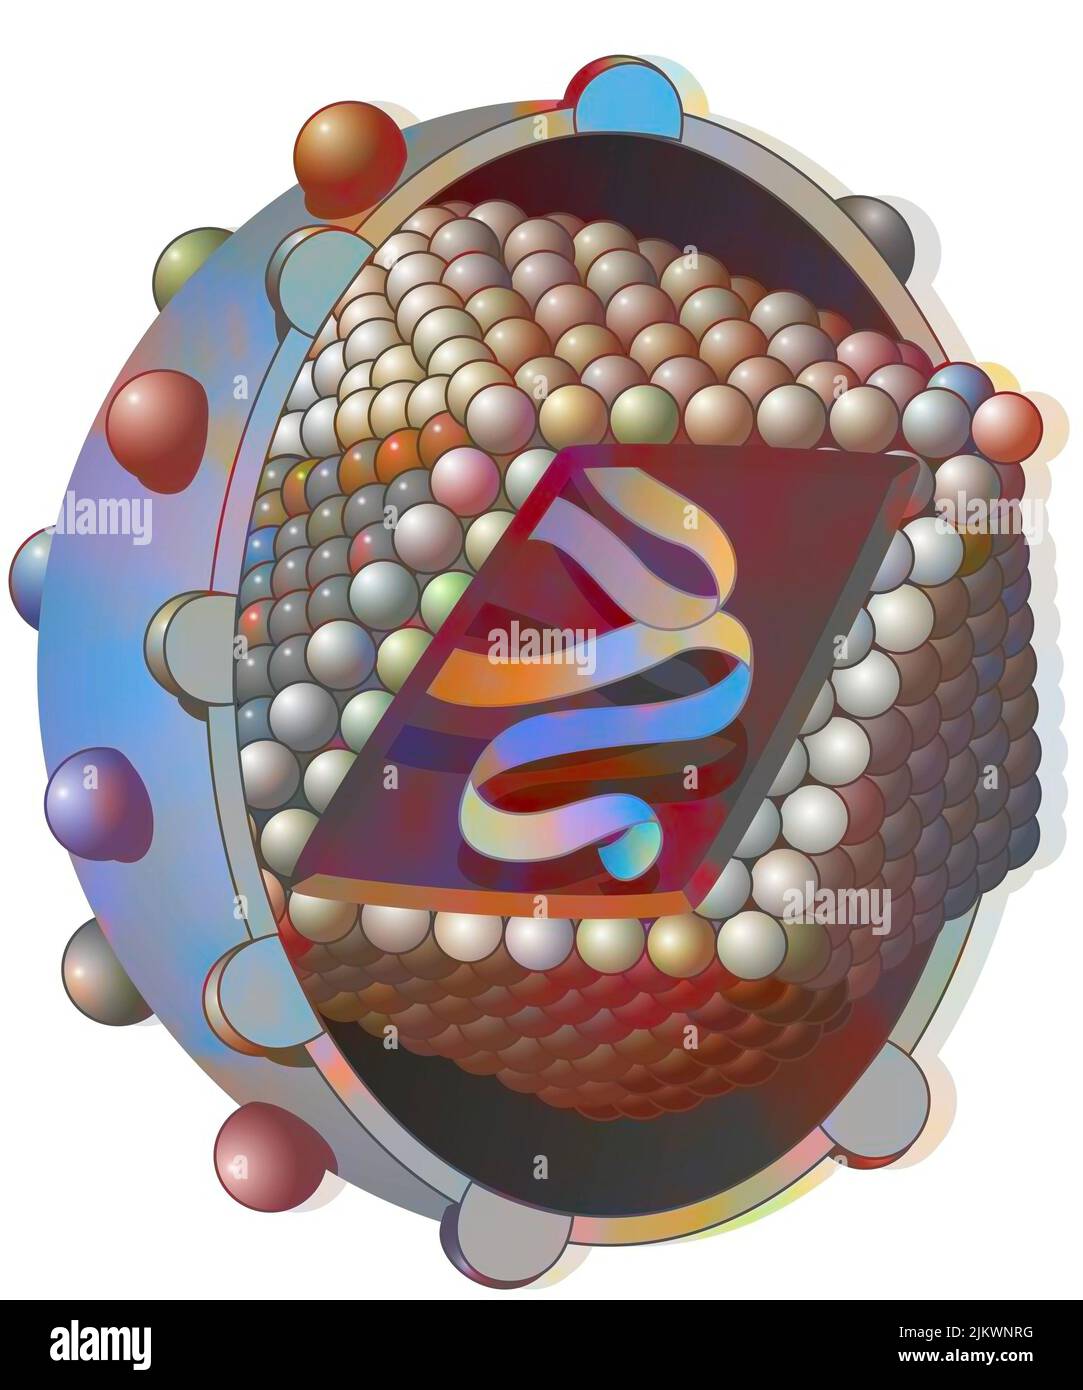

RF2JKWPGK–Acide aminé non synthétisé par la voie du ribosome dont seul l'acide de gauche peut être synthétisé par les ribosomes. C'est pourquoi la synthèse des antibiotiques est si complexe.